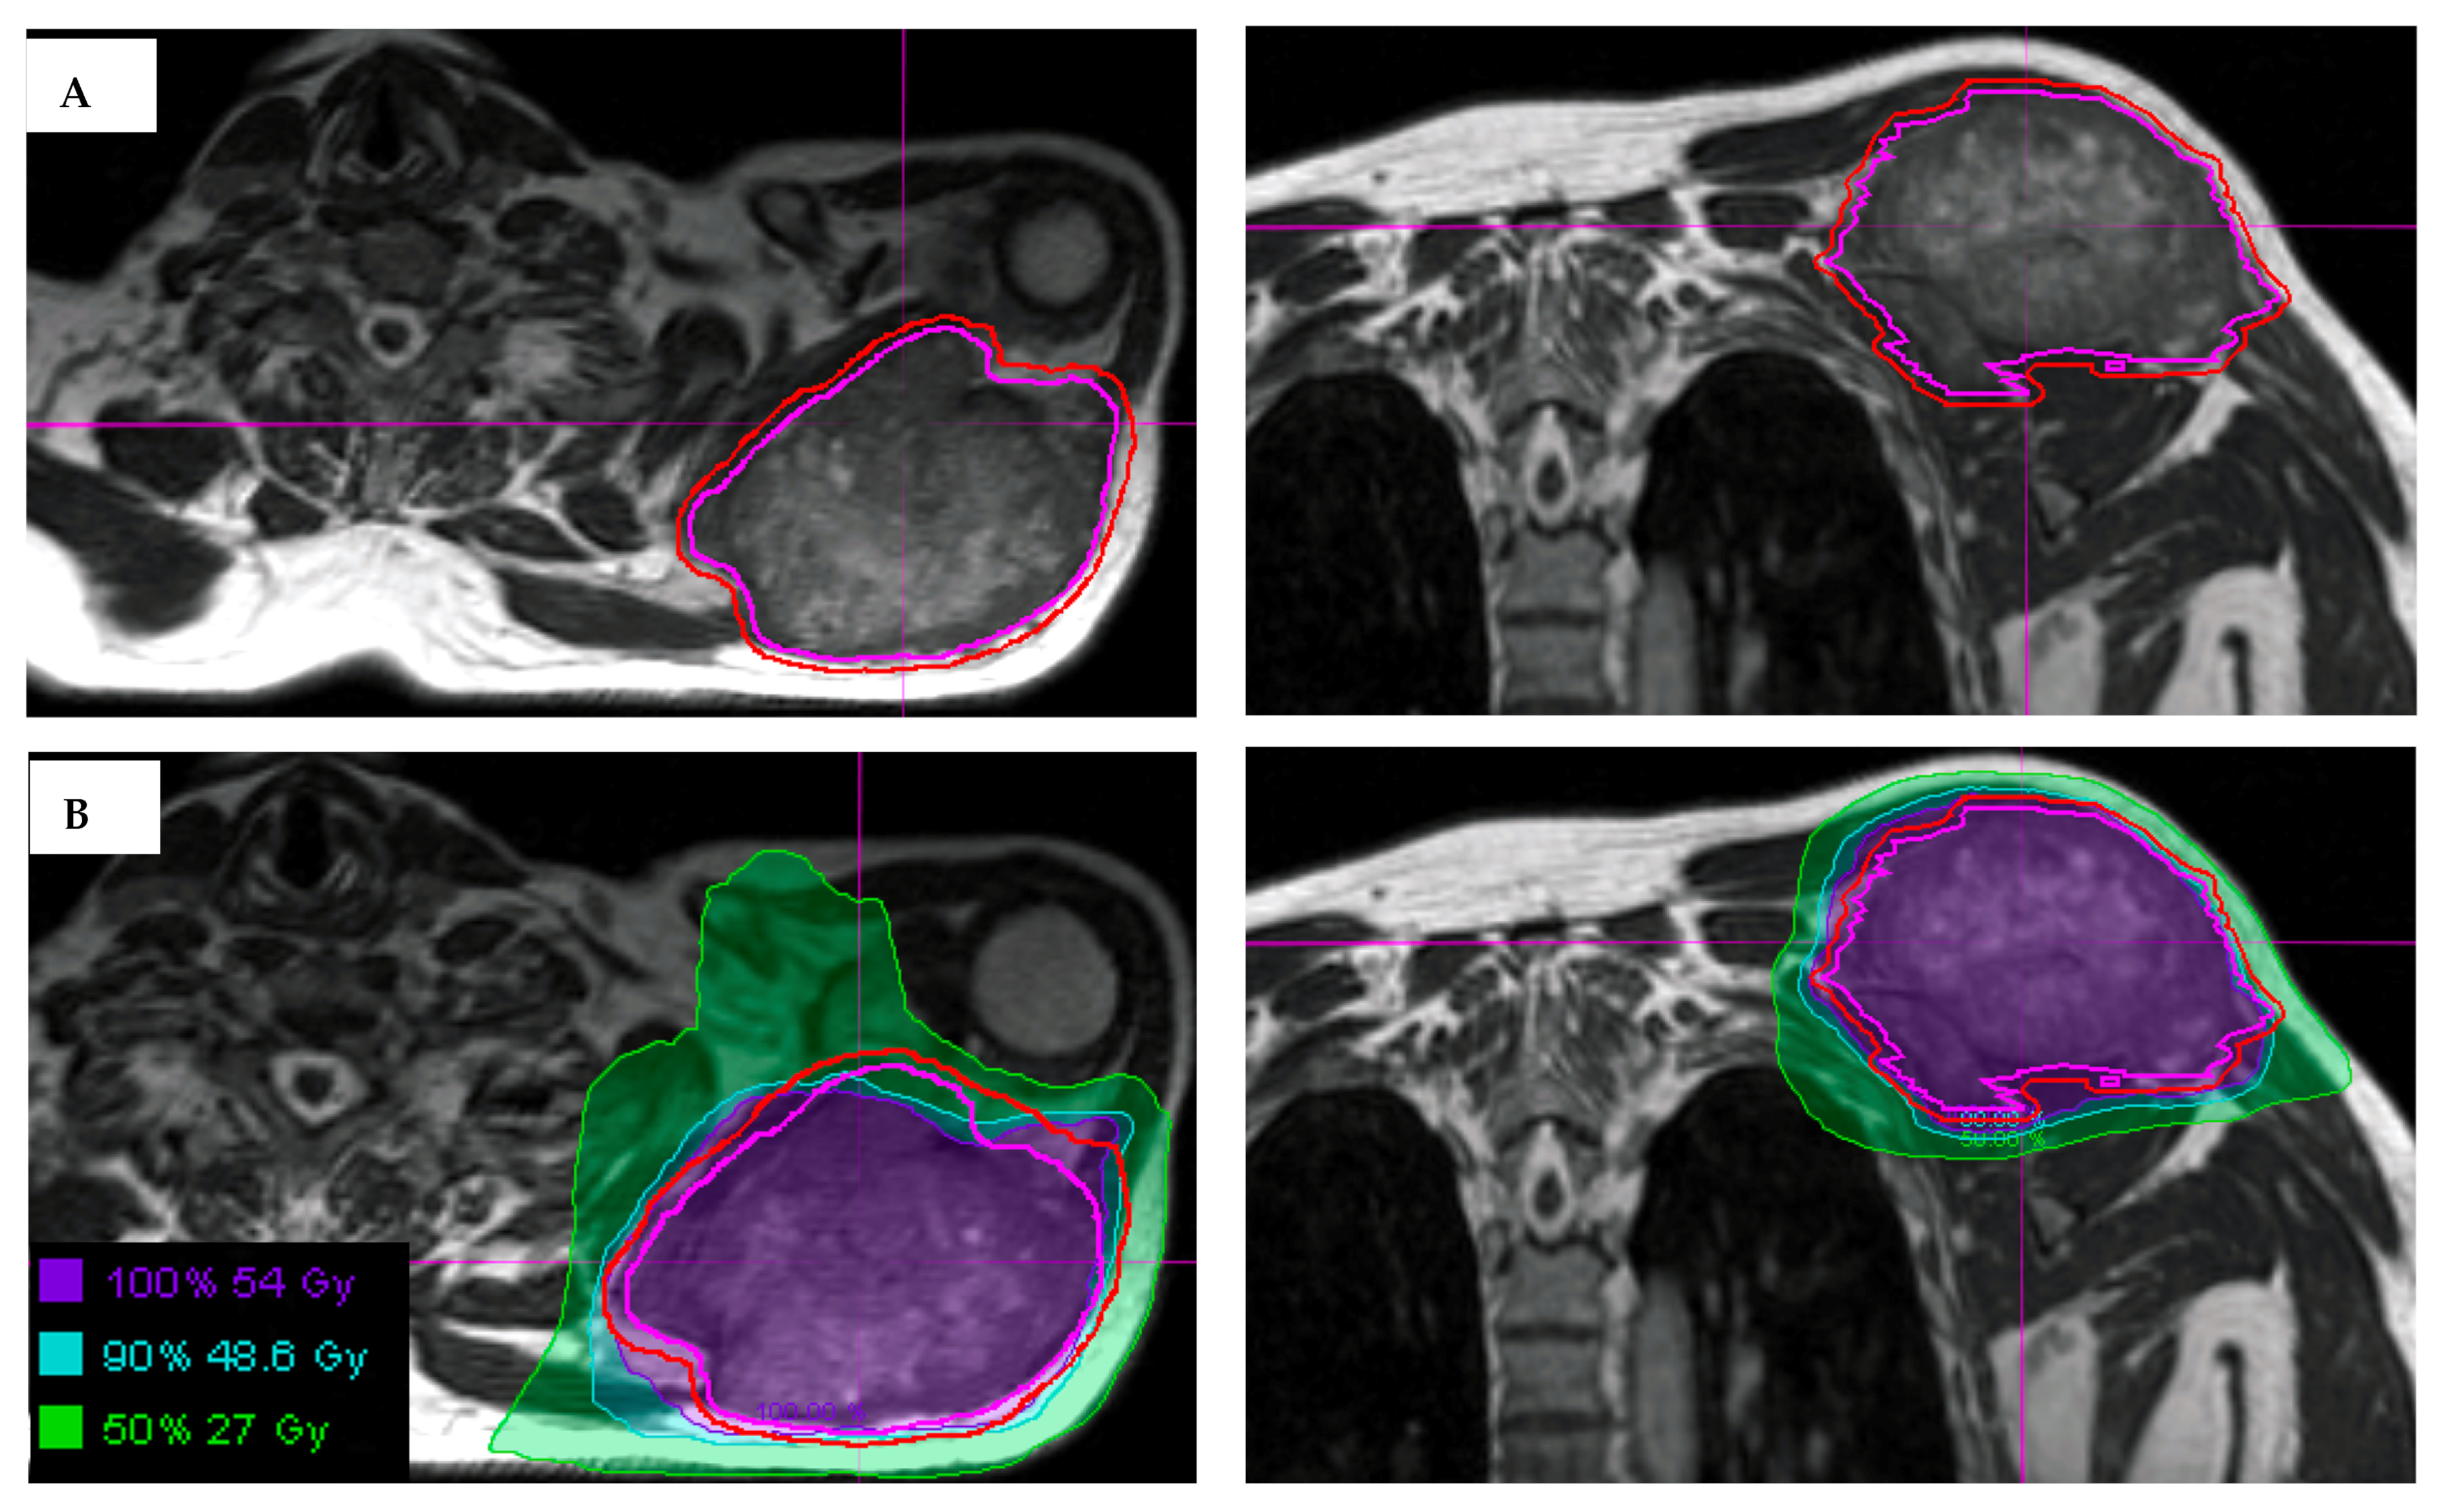

Figure 2. (A) Visualization of an STS and normal tissues in the upper extremity using the 3D True Fast Imaging (TRUFI) sequence on MRI-guided linear accelerator. The gross tumor volume is outlined in magenta, with expansion to planning treatment volume (outlined in red) using small margins, in part due to MRI for daily set-up. (B) Hypofractionated radiation treatment plan for an upper extremity STS showing the use of MRI-guidance to delineate the tumor and the surrounding at risk areas.

Here, we describe three cases of STS that were treated on a phase II clinical trial of hypofractionated radiotherapy for unresectable disease. Each patient had STS that was treated on an MRI-guided linear accelerator. One patient had STS in the upper extremity, one in the lower extremity, and one in the retroperitoneum. The patient with an unresectable upper extremity tumor had angiosarcoma histology with a target volume of 607 cubic centimeters (cc) and received 54 Gy in six fractions. The patient with an unresectable lower extremity tumor had dedifferentiated liposarcoma histology with a target volume was 2689 cc and received 48 Gy in six fractions. The patient with the unresectable retroperitoneal STS had spindle cell histology with a target volume of 81 cc and received 48 Gy in six fractions.

Daily MRI guidance allowed for the safe delivery of high dose hypofractionated radiation, with all patients having no grade 3 or higher acute toxicities. Understanding of potential late toxicity risks is still developing as clinical experience increases with this approach in patients with STS. For each of these patients, radiotherapy planning scans were acquired on 0.35T MRI (MRIdian, Viewray Inc., Mountain View, CA, USA) using a 3D True Fast Imaging (TRUFI) sequence, with 3 mm slice thickness and 40 cm × 40 cm × 43 cm field of view. A daily fractional MRI was acquired using the same imaging protocol to aid treatment set-up. In the case of the patient with STS of the lower extremity, MRI imaging enabled reproducibility of the positioning required to target the mobile lower extremity while avoiding the contralateral leg (Figure 1). In the case of the patient with STS of the upper extremity, MRI imaging ensured an accurate daily set-up and target delineation both for the planning and for each treatment (Figure 2). In the case of the patient with a retroperitoneal STS, daily MRI visualization allowed for adaptive planning which optimized tumor coverage while reducing dose to nearby organs at risk including bowel and kidney (Figure 3). Daily adaptation requires editing the OARs and/or PTV and re-optimizing the planned dose. Patients undergoing adaptive radiation are scheduled for 60 to 90 min. Based on the size of the lesion, editing contours may take approximately 10–20 min, re-optimization and plan review process may take additional 6–9 min.

In all cases, these large STS tumors were safely treated using hypofractionated radiation therapy. The patients with extremity STS had follow-up imaging demonstrating stable disease without local progression at 3 and 9 months for the cases of lower extremity STS and upper extremity STS, respectively. The patient with retroperitoneal STS had partial response on 6-month follow-up imaging. The use of MRI for daily set-up allowed for 0.3 mm PTV margins to be used for this patient, potentially decreasing the toxicity of the plan while affording confidence in tumor and OAR visualization and dosimetry.